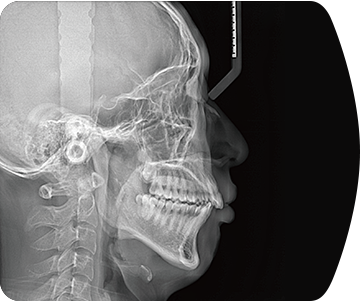

采用高性能CMOS探测器,最大FOV可达16x9cm星垂视野并支持无极可调,最小体素0.05mm。头颅采集模式,支持3s超快速扫描,最小像素99um,保证优质影像快速采集。

标配专业正畸软件

支持自动描点功能

精准定位

真人正侧位投影,实现CT成像区域无极可调